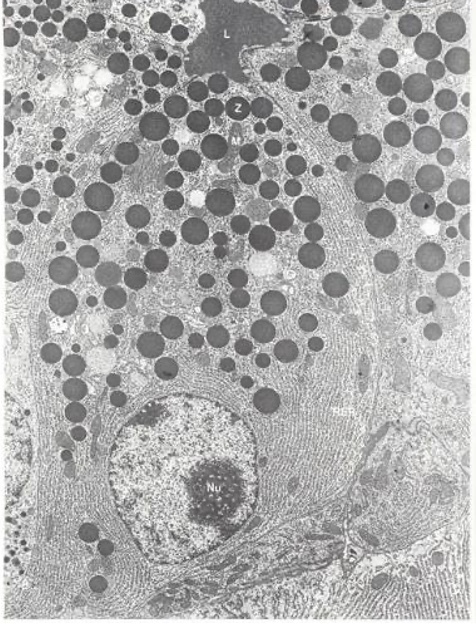

What is a zymogen?

A

• Pancreatic enzymes are packaged within zymogen granules (Z), which can be secreted upon stimulation of the acinar cell

• The enzymes within the zymogen granules are inactive precursors of the mature enzyme (zymogens) to prevent autodigestion of the cell